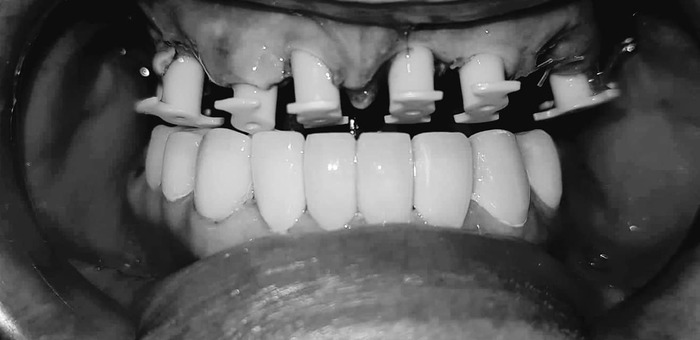

На следующий день мне спреем обезболили верхние десны и Гоча снял финальный слепок челюсти. 5 числа вечером мне одели и за полтора часа подогнали верхнюю челюсть так, что когда я пришел на контрольный осмотр 6 числа - мне ничего подтачивать не пришлось. Гоча - мастер не меньший, чем Георгий и Хатуна.

В итоге - в стоимость в 6000 долларов мне вошли работы по благоустройству переднего ряда нижней челюсти, а через год в ту же стоимость кроме новой нижней челюсти войдет работа по перебазированию верхней челюсти.

А это - мои новые зубы:

Буду учиться по новой улыбаться, есть и разговаривать - с кем из родственников говорил - отмечают, что с шипящими у меня некоторые проблемы еще есть; но, думаю, с разговорной практикой все наладится.